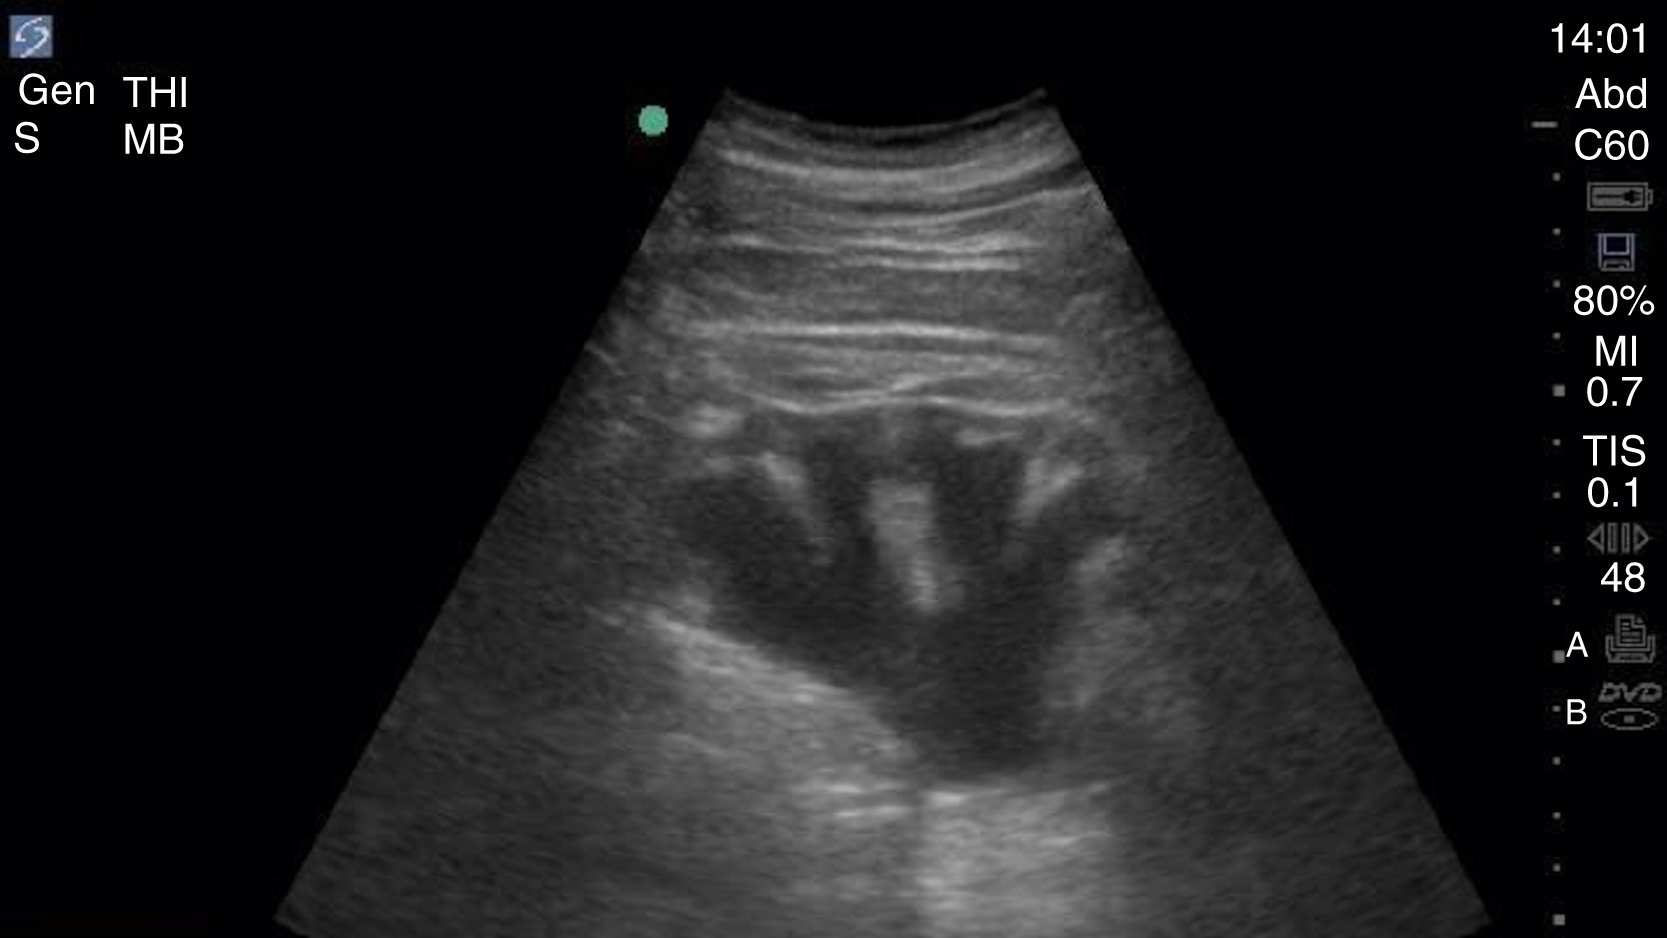

Pathology

Hydronephrosis is characterized by dilation and anechoic fluid accumulation within the renal pelvis and calyces, ranging from mild to severe ( Fig. e3.6 ). Renal and/or ureteral calculi may be identified as echogenic foci with associated shadowing and are usually located within the kidney (nonobstructive) or in the renal pelvis, proximal ureter, or uretero-vesicular junction. Color Doppler placed over the kidney can help differentiate mild hydronephrosis from the renal vasculature, as well as possibly accentuate any renal stones by producing the renal twinkle artifact.

Hydronephrosis with dilation of the calyces and renal pelvis of the kidney showing thinning of the cortex, signifying severe hydronephrosis.